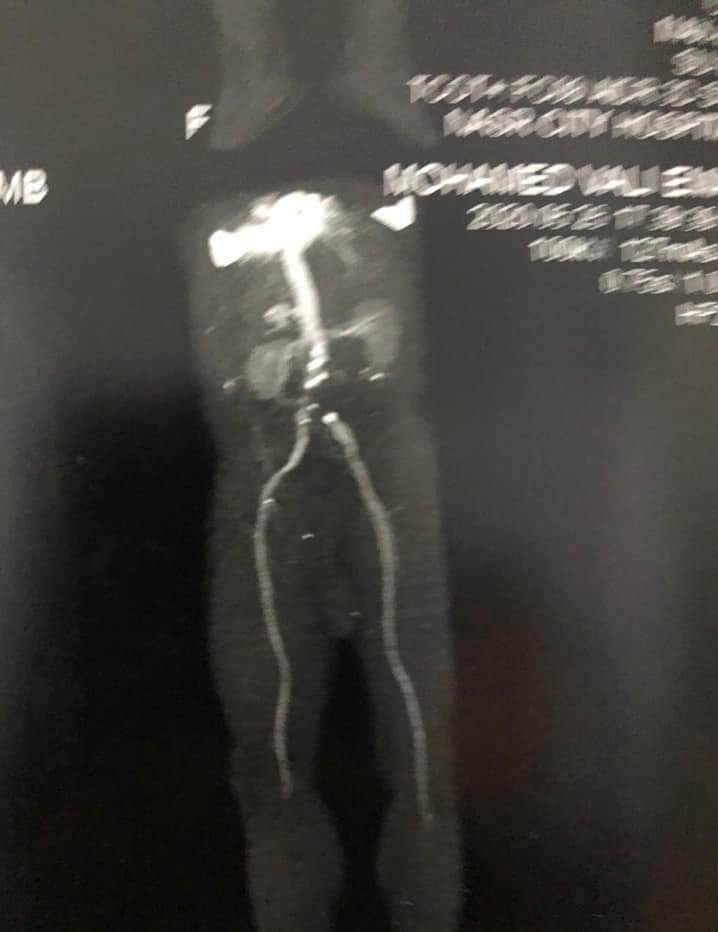

هذه العملية الجراحية العاجلة، عبارة عن تسليك لجلطة حادة بالشريان الأورطي بالبطن، وشرايين كلتا الساقين، وذلك لإنقاذ ساقي المريض من البتر الحتمي، حيث يبلغ من العمر 59 عاما، ويدعى محمد علي، حيث بينت الفحوصات وجود انسداد كامل في الشرايين.